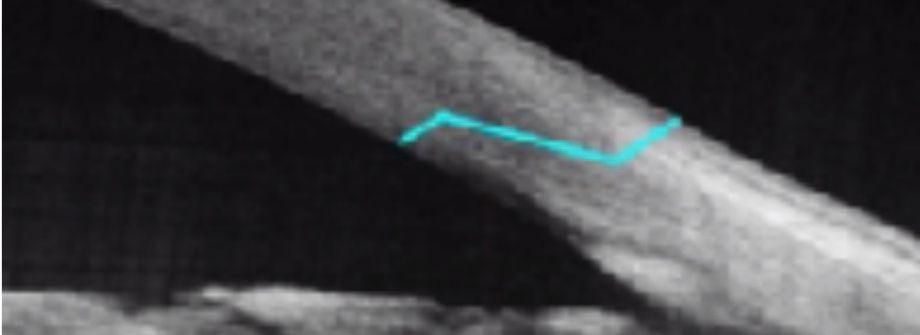

Anche all’OCT si nota l’ombra della IOL adagiata in fovea.

L’esame ecografico mostra la presenza della IOL lussata adagiata sulla superficie retinica in sede foveale.